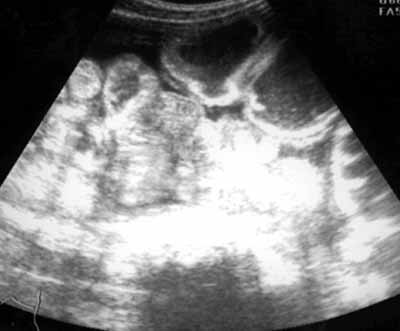

Ультразвуковое исследование в диагностике тонкокишечной непроходимости.

Рис. 3. Эхограмма того же больного. Расширенные петли тонкой кишки сдавливают спавшиеся петли подвздошной кишки, расположенные дистальнее места обструкции.

Новости лучевой диагностики 2002 1-2: 32-34